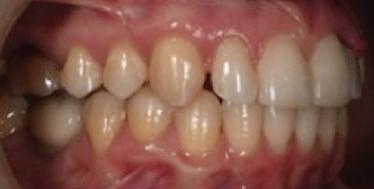

Dental Tribune Bulgarian Edition / октомври 2022 г.16 клиничен случай с алайнери Г орният латерален ре зец е вторият найчесто вродено липсващ зъб.1,2 Поради разполо жението му във видимата зона на усмивката лечение то на подобни случаи нала га мултидисциплинарен под ход, целящ отличен функцио нален и естетичен резултат. Налице са няколко лечебни мо далности, свързани с различ но разпределение на място то: първият вариант е орто донтско отваряне на място и възстановяване на липсва щия зъб с конструкция, под държана от съседните зъби3 или от имплант4, докато при втория подход разстоянията се затварят и премоларът заема мястото на канина.5 Изборът на лечебен подход трябва да бъде направен съв местно от зъболекар и паци ент въз основа на очакванията на последния и предвиди мостта на лечението. Множе ство фактори влияят върху това решение, като напри мер типа малоклузия, размера, формата и цвета на кучеш ките зъби6, оклузалните вза имоотношения (овърджет и овърбайт), лицевия профил, дължината на зъбната дъга и несъответствията в разме ра на зъбите.7 В настоящата публикация се разглежда случаят на жена в зряла възраст с вродена лип са на горен ляв латерален резец. Бяха приложени про зрачни алайнери за отваряне на място за единичен им плант и бяха постигна ти функционална оклузия и отлична естетика. ПРЕДСТАВЯНЕ НА СЛУЧАЯ Диагноза Пациентката бе на 32 годи ни, когато лечението започна, и първоначалното ѝ състоя ние бе следното (фиг. 1–3): липсващ горен ляв латерален резец; клас II, подклас I малоклузия; отклонение на горната сре динна линия вляво; Доклад на клиничен случай ЛЕЧЕНИЕ С АЛАЙНЕРИ НА ПАЦИЕНТ С АГЕНЕЗИЯ НА ЛАТЕРАЛЕН РЕЗЕЦ Д-р Iro Eleftheriadi и д-р Christodoulos Laspos, Гърция и Кипър Фиг. 1a–h Предоперативни лицеви и интраорални снимки. Фиг. 2a–e Дигитални модели преди началото на лечението. Фиг. 3 Панорамна снимка преди лечението. Фиг. 1a Фиг. 1d Фиг. 1f Фиг. 2a Фиг. 2d Фиг. 2b Фиг. 2e Фиг. 3 Фиг. 2c Фиг. 1b Фиг. 1e Фиг. 1g Фиг. 1h Фиг. 1c

Dental Tribune Bulgarian Edition / октомври 2022 г. 17клиничен случай с алайнери леко струпване в долната че люст; несъответствие по Болтън (мандибуларен излишък от 3.06 мм във фронталната зона и общо 1.47 мм); издължено лице с лицева аси метрия; конвексен профил с ретруди рана долна челюст и проми нентен нос. На мястото на зъб #46 бе на лице имплант, а зъби #16 и 26 са ендодонтски лекувани. Тези зъби бяха асимптоматич ни, затова бе взето решение да се прави релечение само при нужда. Мъдреците липсваха. Анализът на телерентгеногра фията (фиг. 4) показа ретрог натна мандибула (SNB: 74.2°) и нормална инклинация на резците както в